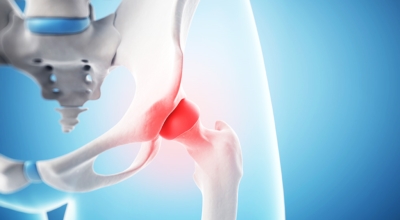

고관절이란 골반을 지탱하는 관절로서 근육과 힘줄로 구성되어 있습니다. 학계에서는 고관절을 엉덩이 관절이라고 부르기도 하며 인체의 하중을 지탱하는 아주 주요한 관절입니다. 각별히 고관절은 우리가 정상적으로 서있거나 움직일 수 있게 만들어주고 달리기, 점프, 무거운 무게를 들 때 최대 체중의 2~10배 가량의 하중을 받기 때문에 적절한 관리가 필요해요. 오늘은 고관절에서 생기게 될 수 있는 고관절 통증 증상에 대하여 알려드릴게요.

고관절염은 고관절에 나타나는 관절염을 말하며 고관절의 연골이 닳게 되면서 뼈와 뼈가 서로 부딪히며 통증을 일으키게 됩니다. 고관절염 초기 증상으로는 사타구니 부위가 불편하게 느껴지며, 무리하면 통증이 생길 수 있다고 하며, 관절염 증상이 심해지면서 사타구니에서 느끼던 통증이 허벅지와 엉덩이 통증으로 이어지기도 하는데, 고관절염 통증 증상으로 초기에는 허리 통증이 나타나 허리 질환과 혼동하기 쉬우며 각별히 척추질환이 있는 사람은 고관절 통증 증상과 마찬가지로 엉덩이, 다리 통증이 동반되기 때문에 훨씬 헷갈리는 경우가 많다고 해요.

나이가 들면 통상적으로 발생되는 질환 중 한 종류입니다. 관절을 지켜주며 있는 연골의 훼손이나 퇴행성 변화로 인해 관절을 이루는 뼈와 인대 등에 훼손이 생겨 염증과 통증이 나타나는 질환입니다. 고관절 쪽 연골이 닳게 되면서 망가지게 되고 또 쉽게 끊이지 않는 통증에 시달릴 수 있습니다.